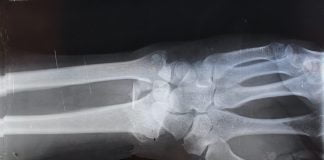

Ce trebuie sa stim despre refacerea oaselor?

Refacerea oaselor este un proces esential pentru buna dezvoltare si evolutia medicala, sociala sau chiar economica a individului. Cel mai adesea osul se reface...